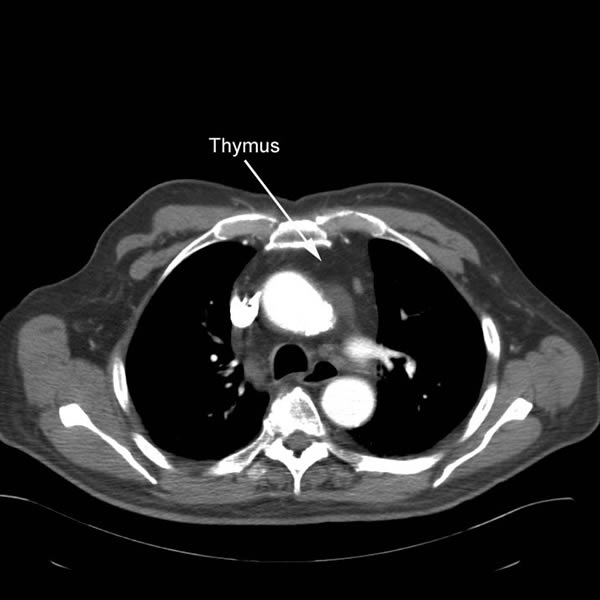

| Figure 6: Complete thymus removed. |

The gland is grasped in the midline at the level of the innominate vein and retracted anteriorly and to the left and the posterior aspect of the gland dissected sharply to the AP window. Once this is complete the left upper margin of the gland is dissected anteriorly from the phrenic nerve in the region of the AP window. With this the gland is freed from the mediastinum and is removed through the cervical incision (Video 11, Figure 6). Any remaining anterior mediastinal and pericardial fat is removed (Video 12). At the conclusion of the operation the entire anterior mediastinum should be clear of thymic tissue and fat (Video 13). A medium sized Blake or JP drain is placed and the lung is re-inflated (Video 14).